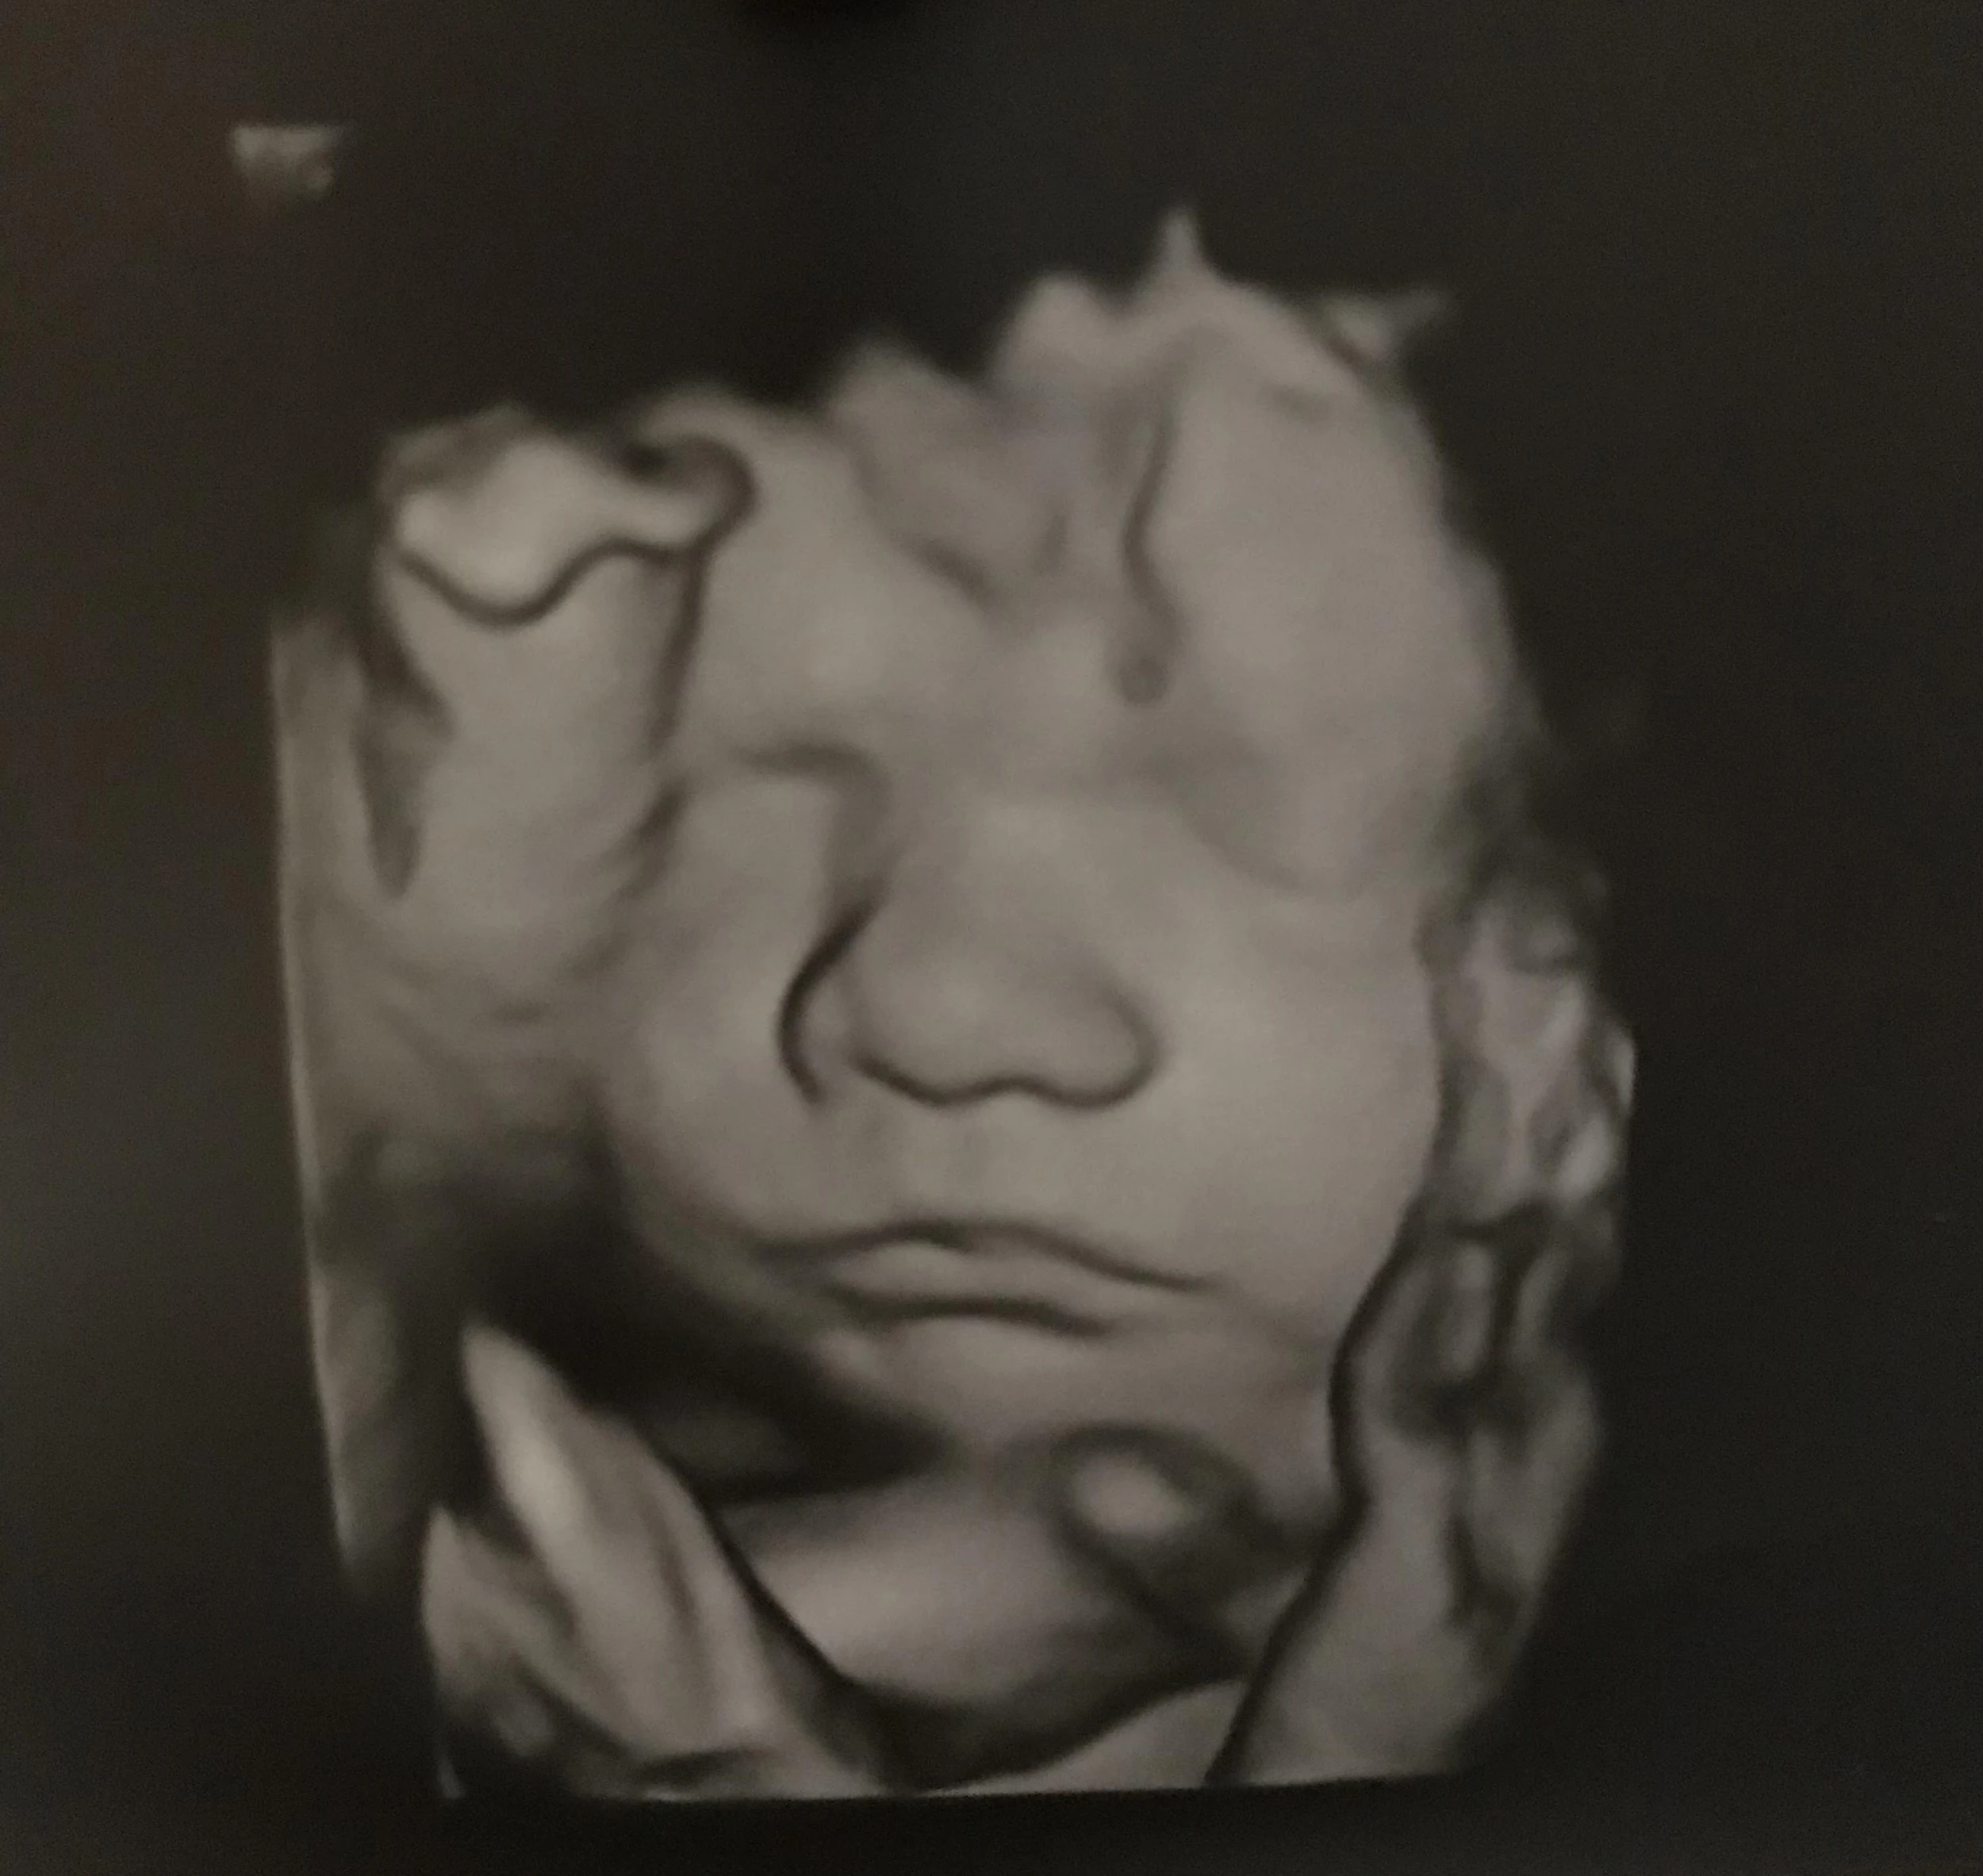

A mostani alkalommal is mindent rendben talált az orvos, azt mondta, hogy minden érték tökéletes. Szép nagy babának ígérkezik, hiszen a méretei 1 héttel idősebbnek felelnek meg, mint amennyi valójában. Jó érzés volt újra látni, ahogy odabent mocorog és kaptunk egy újabb fotót is szerelmünk gyümölcséről.